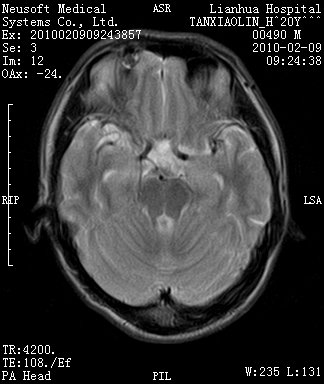

20岁男性患者,平时偶有头痛而无其他不适,现因持续头痛服药后无缓解而来院就诊。

松果体囊肿?

松果体区占位继发轻度脑积水?该患者有ct资料,我已发上。

考虑松果体囊肿。